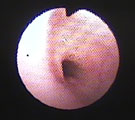

初診時頸胸部X線所見。頚部気管狭小化が認められた。 気管支鏡所見。喉頭直下の狭窄。全周性粘膜肥厚、凹凸不整あり。 粘膜肥厚部の病理組織所見。間質に軽度の線維化を伴ったリンパ球主体の炎症細胞浸潤あり。 Tチューブ設置後頸胸部X線所見。気管開存し、努力呼吸が消失した。

経過:受診時、T:37.4℃、P:138/分、R: 28。著しい吸気努力。吸気時に頚部気管中央部に強い高音調喘鳴音あり。頚部触診にてマス病変なし。SpO2<90%。血液ガス分析にてpHa 7.34, Paco2 56 mmHg, Pao2 64 mmHg, [HCO3-] 29.4 mmol/L, A-aDo2 19 mmHgと、重度な肺胞低換気所見を示した。肺機能には異常なく、中枢気道閉塞によると考えられ、気道開存処置で症状改善することが見込まれた。ただちに酸素室管理とした。同日、気管支鏡検査にて喉頭直下に全周性粘膜肥厚と粘膜表面の凹凸不整がみられた。最狭窄部を気管切開後、外径6mmのTチューブを設置した。術後、呼吸困難は消失した。気管支鏡下粘膜生検にて、間質に軽度の線維化を伴ったリンパ球主体の炎症細胞浸潤の病理組織所見が得られた。生検標本洗浄液の培養にて菌は検出されなかった。気道ステント処置に加え、ネブライゼーション(ステロイド、エピネフリン、抗生剤)およびステロイド・CPシロップ内服にて術後管理を行った。術後10日目に、血液ガス分析にてpHa 7.34, Paco2 30 mmHg, Pao2 95 mmHg, [HCO3-] 15.8 mmol/L, A-aDo2 18 mmHgと、肺胞低換気所見は消失し、正常化したので、退院とし自宅管理となった。2ヶ月後に、気管支鏡検査で内部観察後、可能であればTチューブを抜去を試みることになった。